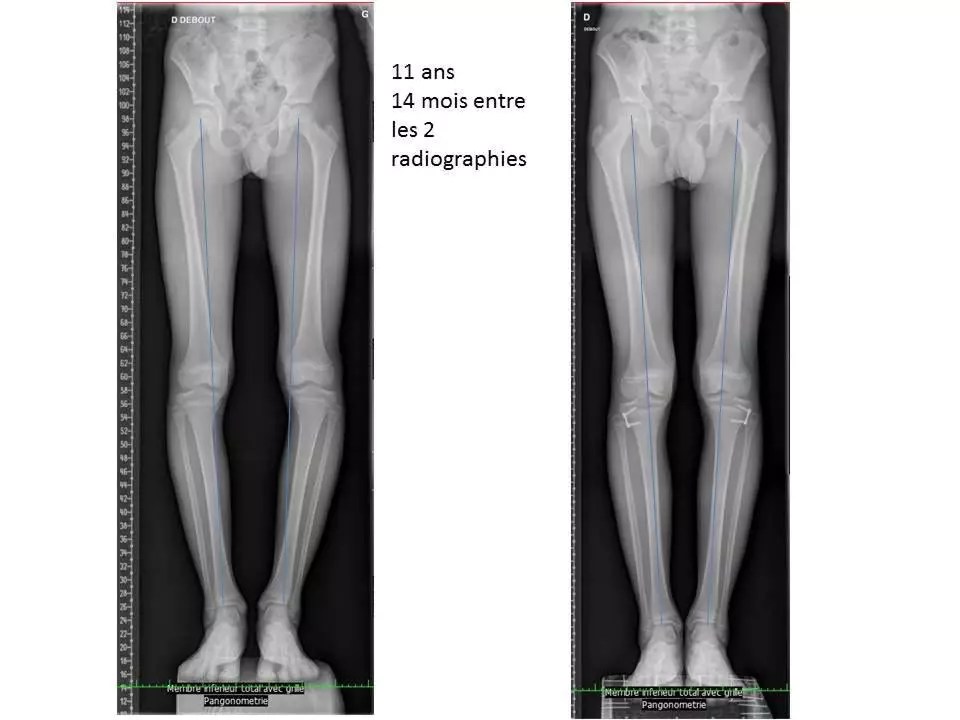

From orthopedie-pediatrique.com

Les déviations des genoux, genu varum et genu valgum Correction Genoux En X Le genu valgum, également connu sous le nom de “jambes en x”, est une déformation du membre inférieur qui peut avoir des implications esthétiques et pathologiques. Communément appelés jambes en “x” ou en ciseaux, les genoux valgus sont généralement présents dès l’enfance. Le genu valgum désigne une déviation des genoux vers l’intérieur. Le genu valgum, aussi appelé jambes en x,. Correction Genoux En X.